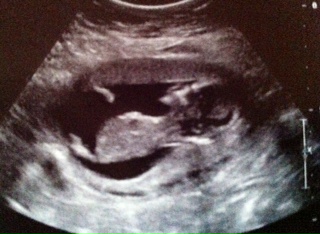

Hi ladies! I cannot tell if this is a picture of the cord or the nub. I'm not good at deciphering these at all. Any gender guesses would be awesome! This was taken at 13 weeks. Thanks :)

I can't see a nub in this picture sorry xox

if that is a nub you will be giving birth to Ron Jeremy soon LOL!!

I don't see any gender clues, I'm sorry.